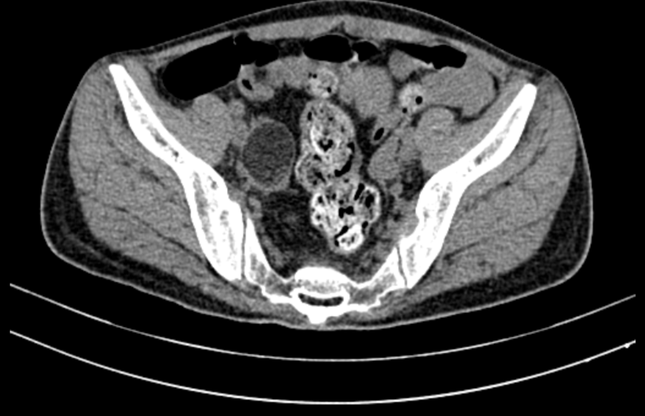

Hình ảnh khối u quái buồng trứng bên phải - nguyên nhân gây bệnh lý viêm não tự miễn cho bệnh nhân (ảnh: BVCC)

Qua chẩn đoán hình ảnh, các bác sĩ phát hiện bệnh nhân bị khối u ở buồng trứng. Kết quả sinh thiết tế bào dưới kính hiển vi cho thấy đây là dạng u quái - nguyên nhân gây bệnh viêm não tự miễn kháng thể kháng thụ thể NMDA ở phụ nữ. Sau 7 lần thay huyết tương, người bệnh được phẫu thuật nội soi cắt u quái thành công. Gần 1 tháng sau cuộc mổ, sức khỏe của người bệnh đã bình phục tốt, đủ điều kiện xuất viện.